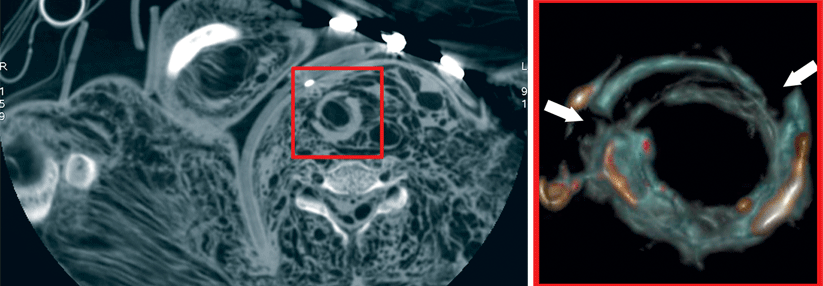

CT bei Verdacht auf COPD (links) und darübergelegtes qCT (rechts).

Blau: Areale mit gefangener Luft, rot: Gefäße.

Die quantitative Computertomographie (qCT) geht weiter und interpretiert jeden einzelnen Bildpunkt separat als Gitterpunkt im dreidimensionalen Raum. Das kann etwa bei der COPD wertvolle zusätzliche Informationen liefern, wie Dr. Joshua Gawlitza, Universität Mannheim, auf dem 99. Deutschen Röntgenkongress berichtete: „Mit der qCT können wir die schlecht belüfteten Lungenareale erkennen.“ Selbst Rückschlüsse auf die Lungenfunktion sind mit dem Verfahren möglich.

Dazu füttern die Forscher ein neuronales Netzwerk mit qCT-Parametern wie dem Lungenvolumen, der mittleren Lungendichte und dem Anteil schlecht belüfteter Areale. „Die Software errechnet die Lungenfunktion anhand unterschiedlicher Modelle und bildet einen Mittelwert. Den vergleichen wir dann mit den Ergebnissen aus der Bodyplethysmographie, dem Goldstandard.“ Erste Ergebnisse zeigen, dass die so erhaltenen Lungenfunktionsparameter FEV1/VC oder RV/TLC nur um etwa 10 % von den Werten der Ganzkörperplethysmographie abweichen.